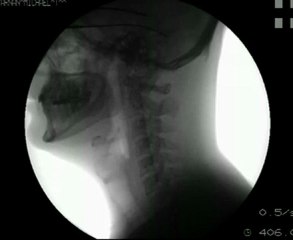

Mâcher et avaler de la nourriture filmé aux rayons X